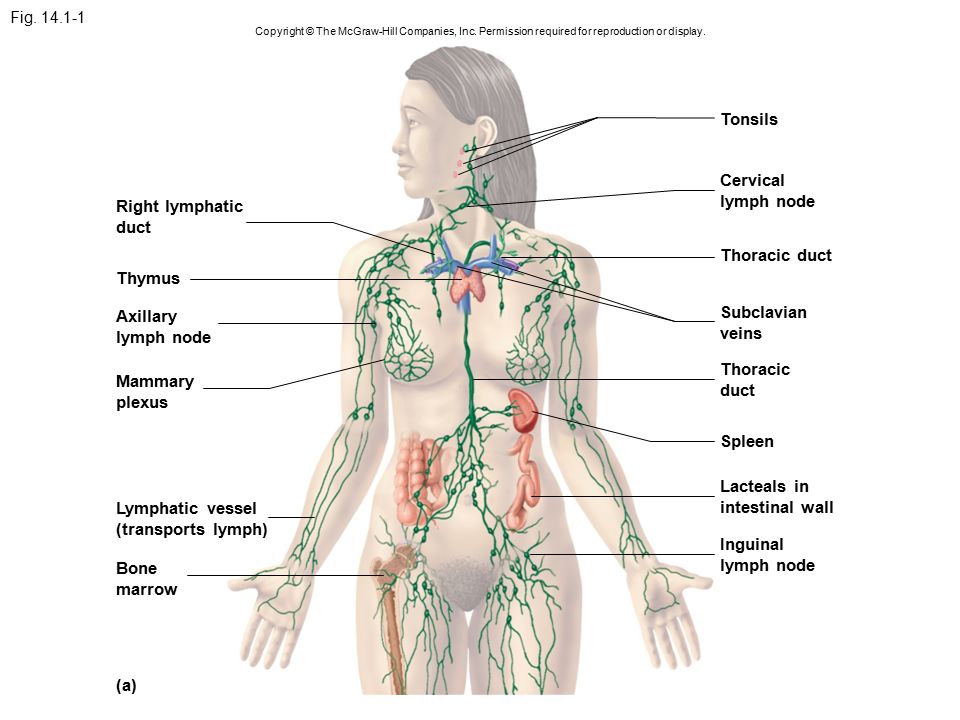

Изображения и схемы: как выглядит лимфа